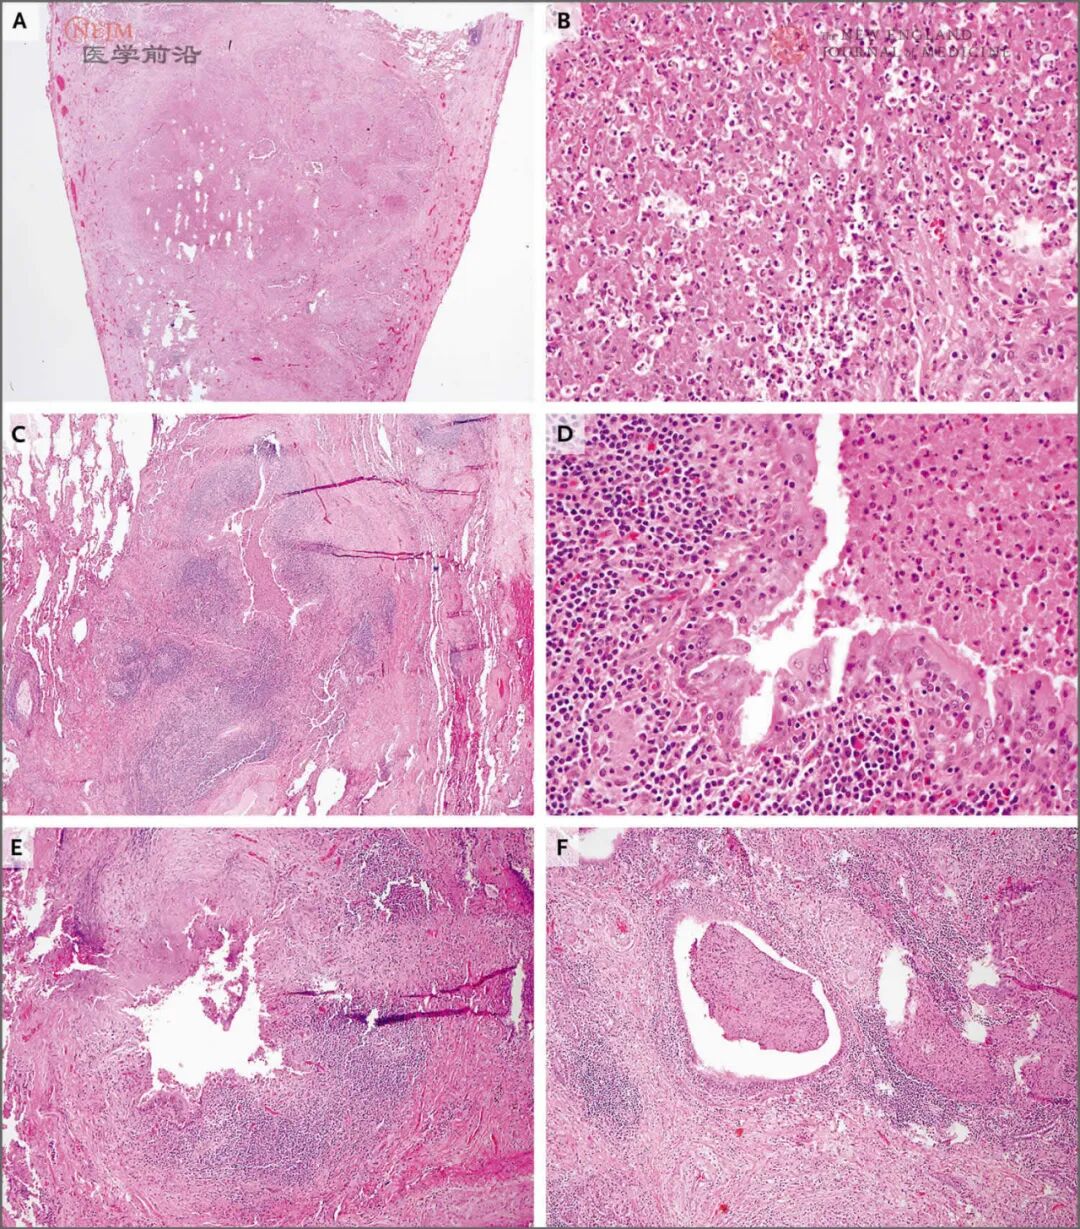

胸部计算机断层扫描(CT)显示支气管扩张累及全部肺叶,但右上叶最严重。上叶气道内可见黏液栓。有散在的“树芽征”,有多个散在的实性肺结节,最大直径1.5 cm。无肺水肿、胸腔积液或者纵隔或肺门淋巴结肿大的证据(图2)。

胸部CT扫描显示支气管扩张累及全部肺叶,但右上叶最显著(白色箭形),右上叶扩张的气道内可见黏液栓(箭头),并有散在的肺结节,最大直径1.5 cm(黑色箭形)。